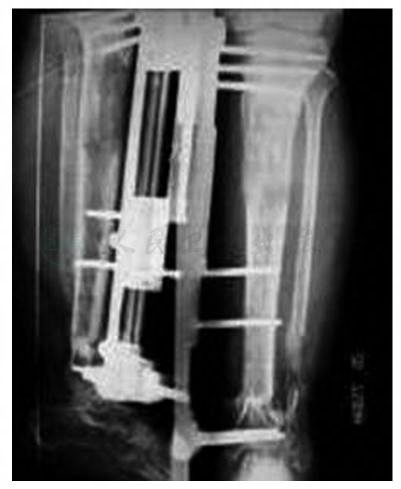

左胫腓骨正、侧位X线片:胫骨远段骨折,胫骨骨折远、近端之间有1段7cm长的腓骨,并以接骨板螺丝钉固定,骨折端间呈向内成角畸形。腓骨远段骨折,复位后以接骨板螺丝钉固定(图4)。右胫腓骨正位X线片示:右腓骨中下段缺如约7cm(图5)。

图4 左胫腓骨正、侧位术前X线片